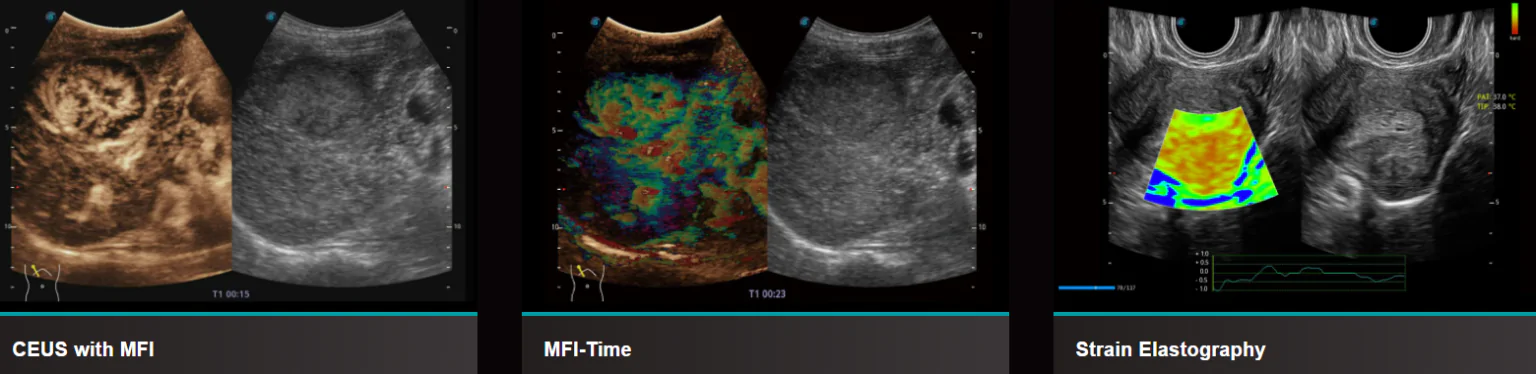

Функции УЗИ системы S50 Elite

- Micro F обеспечивает инновационный метод расширения диапазона видимого потока при ультразвуковом исследовании, особенно для визуализации гемодинамики крошечных сосудов.